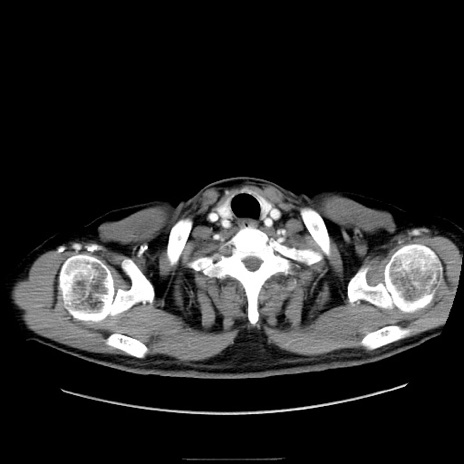

症例30(横断像)

【症例】80歳代男性

【主訴】臍周囲痛

【現病歴】約6時間前から臍下部痛が出現。次第に腹部膨隆・背部痛も生じてきたため来院。背部痛の場所は変化しない。

【身体所見】意識清明、BT 36.3℃、BP  131/87mmHg、P 87bpm、SpO2 100%(RA)、臍周囲自発痛・圧痛あり、反跳痛なし、自発痛部位に一致して板状硬あり、腹部膨隆、腸雑音減弱、CVA tenderness両側陰性。

【データ】WBC 19600、CRP 0.33